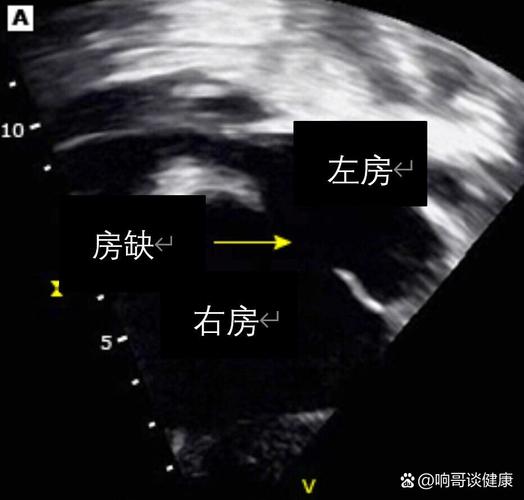

心脏分为左右两侧,左右两侧的心房(心脏的上半部分)之间有一堵墙,叫做“房间隔”,这堵墙的作用是阻止富氧的动脉血和缺氧的静脉血混合。

“房间隔缺损”就是这堵墙上有了一个“洞”,血液会从压力高的左心房流向压力低的右心房,导致一部分本该供给全身的血液没有发挥作用,又回到了肺部,增加了心脏和肺部的负担。

- 复查方式:通常是心脏彩色多普勒超声(心脏彩超),这是一种无创、无痛、没有辐射的检查,就像做B超一样,可以清晰地看到心脏的结构和血流情况。